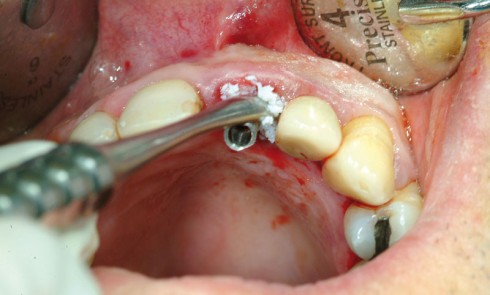

Article réservé à nos abonnés Applications de l’imagerie en chirurgie orale : modalités et indications

Complémentaire et indissociable de l’examen clinique, l’imagerie est essentielle pour l’évaluation diagnostique et la prise en charge thérapeutique en chirurgie...